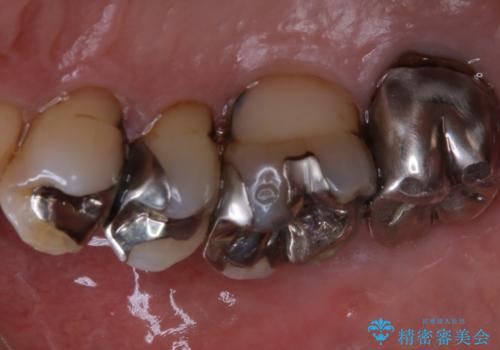

施術後の歯の表面に、茶色く色が残っている所がありますが、これは詰め物の変色の所と、虫歯になっている所です。以前に、CR(コンポジットレジン)による虫歯治療がされています。

CRは経年的劣化や、着色してしまうことがあります。PMTCでクリーニングを行うと、古いCRが目立つことがあるため、気になる際は詰め替えを行います。

茶色くなっている部分が、着色なのか、劣化なのか、虫歯によるものなのかは判別が難しいことがあります。そのため、定期的にPMTCを行うことで状態の確認が的確に行えます。